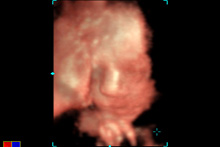

Essa manhã fizemos uma ultrasonografia 3d-4d, foi ótimo ver a Julia novamente e como ela cresceu desde a ultrasom que fizemos com 19 semanas (estou com 27 semanas). Fomos na Siemens, que oferece essas ultras de graça para testar o software de ultrassom deles. Eu realmente não queria gastar $200 para fazer uma ultra 3d-4d porque simplesmente acho a qualidade das imagens uma porcaria, gosto muito mais da ultrasonografia 2d tradicional do que da 3d-4d. Não consigo achar legal, o bebê parece todo deformado, muito bizarro. Mas como era de graça…hehe. Eles nos deram um CD com algumas poucas fotos e uns videozinhos, então vou colocar aqui para vocês verem, mesmo eu achando as imagens estranhíssimas.

Momentos legais: ela estava com a mãozinha na frente do rosto a maior parte do tempo e mexendo a boquinha. Ela estava de perninhas cruzadas! Descobri que o ovo na minha barriga do lado direito que sinto quase o tempo todo é o bumbum dela e os pés estão à esquerda do meu umbigo. E a técnica de ultrassom confirmou que é uma menina mesmo, sem dúvidas. Esqueci de falar antes: vimos o cabelo dela! O cabelinho está compridinho, por isso que deu pra ver, atrás da cabeça, logo acima da nuca.

que linda!!! a que eu gostei mais foi a foto escura que ela está de perfil!! que narizinho mais lindo!!!!

Nao se engane, a ultra 3D mostra sim as feicoes reais do bebe. Claro que qdo nascem ja estao maiores ate, mas eh aquilo mesmo.

Ai que gostoso! Ela é uma fofa e que narizinho mais arribitadinho, digno de uma princesinha. Parabéns! Bjs!

Muito legal a ultra 3d. Essa imagem da Julia de perfil é muito importante. Quando eu fiz, o médico mediu o comprimento do narizinho do Pedro e disse que a medida do nariz (que só é possível com esta imagem), é um dos parâmetros utilizados para determinar se o bebê tem Síndrome de Down, pois estes bebês geralmente tem o nariz bem curtinho, que não é o caso da Julia.